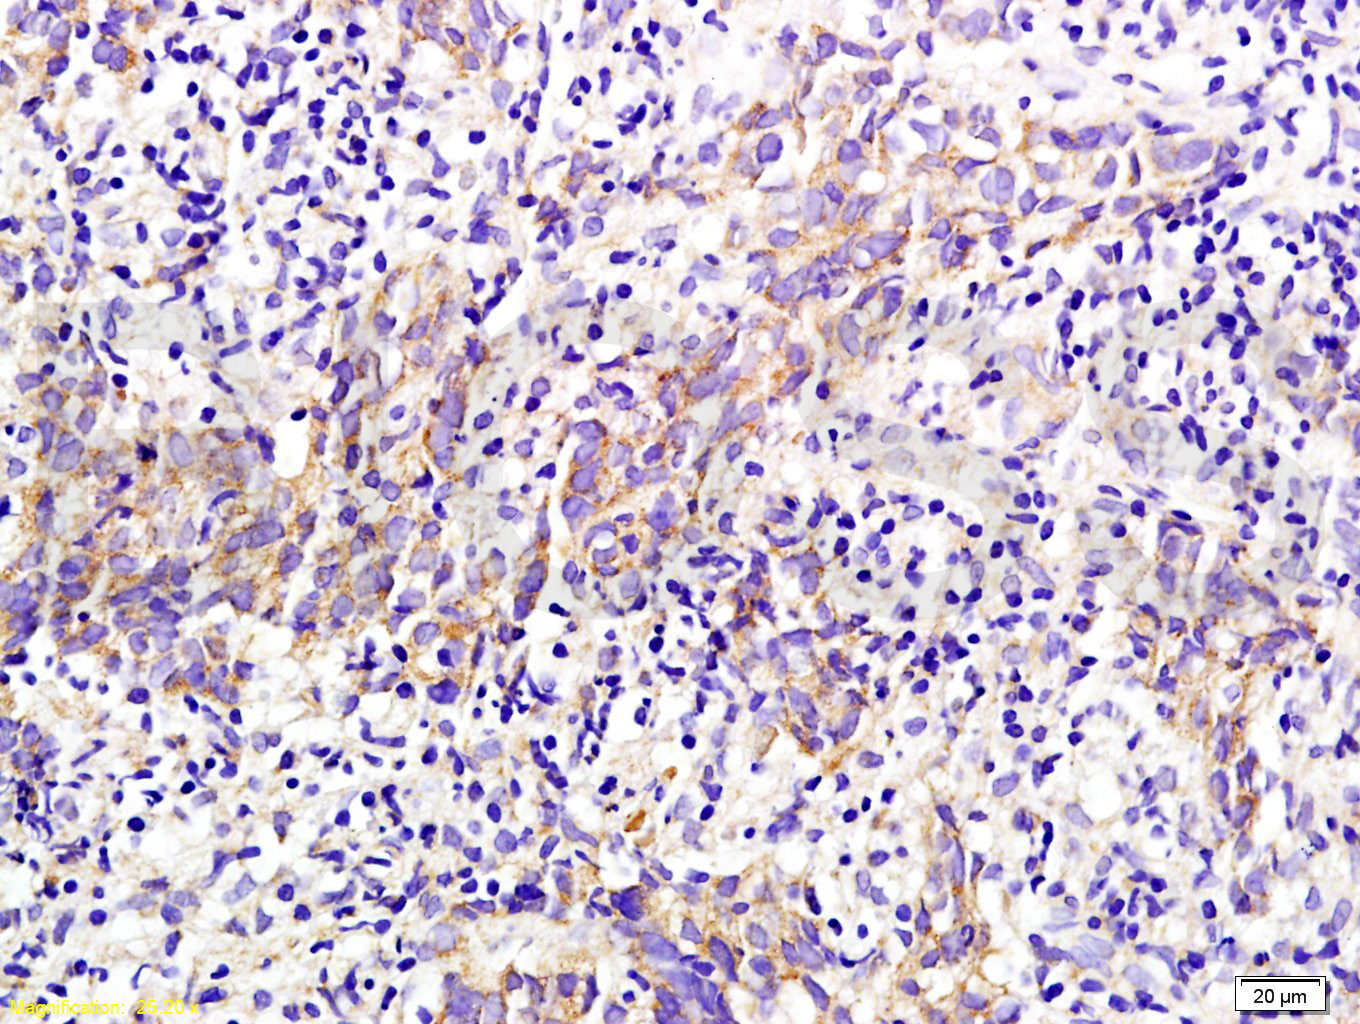

Antigen retrieval: citrate buffer ( 0.01M, pH 6.0 ), Boiling bathing for 15min; Block endogenous peroxidase by 3% Hydrogen peroxide for 30min; Blocking buffer (normal goat serum,C-0005) at 37℃ for 20 min;

Incubation: Anti-M2-PK Polyclonal Antibody, Unconjugated(bs-0102M) 1:200, overnight at 4°C, followed by conjugation to the secondary antibody(SP-0024) and DAB(C-0010) staining